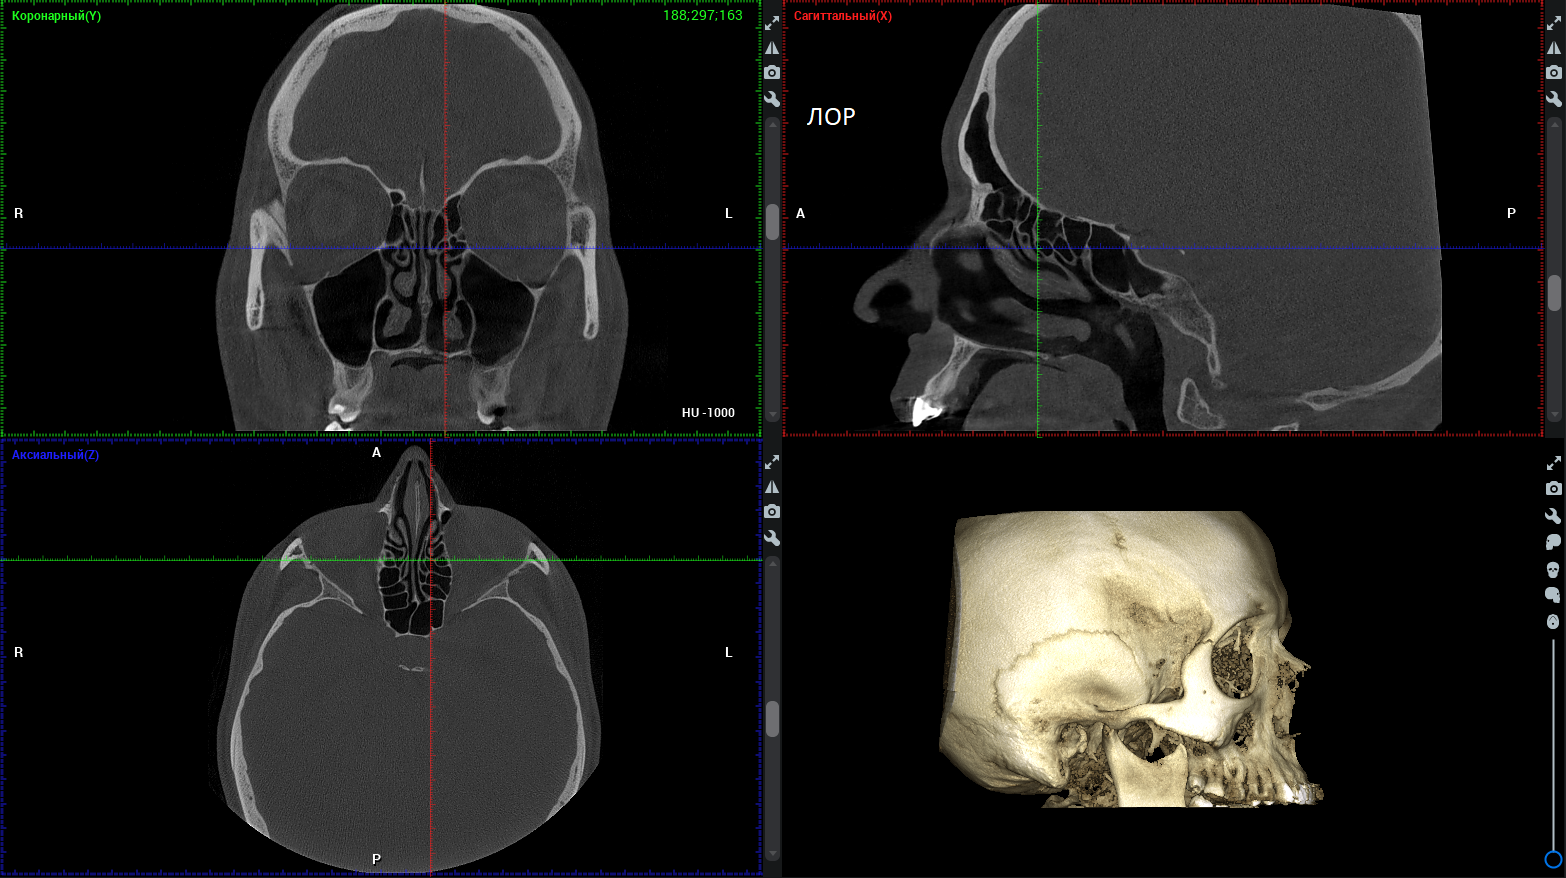

ЛОР-снимки

Связь ЛОР-болезней и заболеваний зубов верхней челюсти – частое явление (например, периодонтит – воспаление тканей вокруг зуба – может осложняться гайморитом). Поэтому на современном ЛОР-снимке и придаточные пазухи носа, и все ткани зубов верхней челюсти должны быть видны идеально.